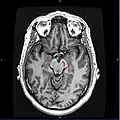

Section through superior colliculus showing substantia nigra.